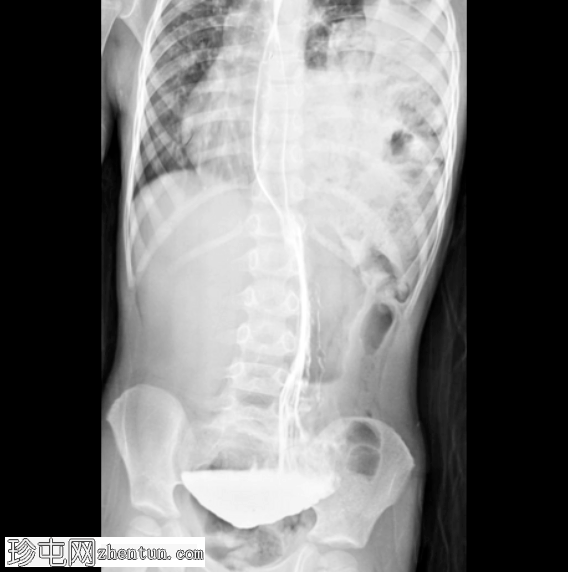

荧光透视

正面

消化道造影检查显示食管口径正常,胃明显延长,延伸至盆腔区域。

左胸腔可见囊性透亮区,与腹部相连,导致心脏轮廓向右侧移位。